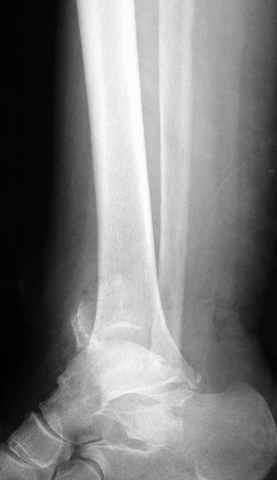

Pilon fracture:

Традиционная техники АО, открытая, с точной репозицией суставной поверхности и жесткой фиксацией, из-за серёзных осложнений, которые

заканчивались ампутацией, уходит в прошлое.

Техника сегодня более щадящая, временные несложные аппараты наружной фиксации: Spanning 2 pin ExFix, Traveling traction для лигаментотаксиса, иначе сокращенные мягкие ткани невозможно восстановить позже.

За последнее 10-12 лет после стабилизации малоберцовой кости, стали применять более усовершенный, сложный, хорошо вам известный метод

Илизарова (кстати наряду с тибиал плато, пилон является одним из показанием по применению аппарата Илизарова при травмах) или Hybrid

Fixator, из минимальных доступов комбинированный метод для восстановления суставной поверхности-фиксация каннулированными

шурупами, создания жесткой системы фиксации до сращения перелома, защита от вальгусной деформации и на место образовавщегося метафизарного дефекта- костная пластика ауто костью или его

синтетические заменители, это сегодняшная тактика лечения.